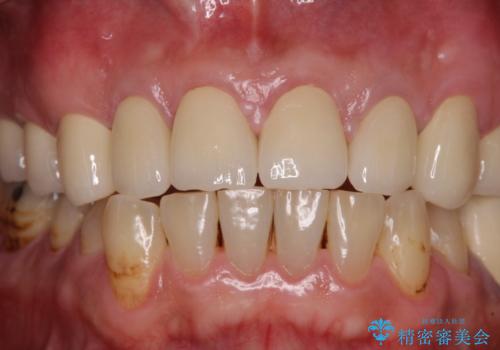

- コンポジットレジンやクラウンなど、様々な医院で治療を受けたために、統一感がなくなってしまった前歯を綺麗にしたいとのことで来院された患者様です。

当初は前歯6歯をオールセラミッククラウンで補綴する予定でしたが、前歯が綺麗に仕上がったことで、奥歯まで延長して補綴することとしました。

黄ばんだ前歯や白すぎたクラウン、プラスチックの継ぎ接ぎなどを全てオールセラミッククラウンの統一感のある前歯に仕上げました。